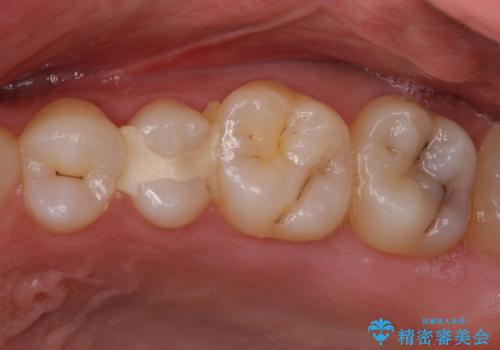

奥歯のクラウン周りが腫れる 精密治療による腫脹の改善